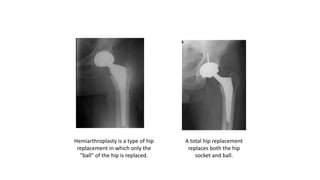

oIn the older patient, the chance that the head of the femur is

damaged in this way is higher. It is generally felt that for these

displaced fractures, patients will do better if some of the components

of the hip are replaced. In some cases, this can mean a replacement

of the ball, or head of the femur (hemiarthroplasty). In other cases,

this can mean the replacement of both the ball and socket, or head of

the femur and acetabulum (total hip replacement).

Hemiarthroplasty is a type of hip

replacement in which only the

"ball" of the hip is replaced.

A total hip replacement

replaces both the hip

socket and ball.